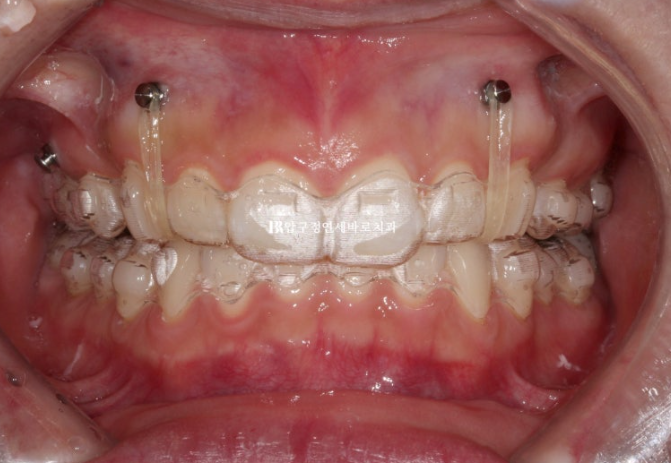

이때부터 거미스마일을 적극적으로 해소하기 위해서 앞니에 미니스크류를 심었고 고무줄을 함께 걸기 시작합니다.

23.07

재제작시 발치공간은 절반정도 남은 상황이였습니다.

24년 7월까지 1년 간 첫번째 추가장치를 다 낀 후 모습입니다.